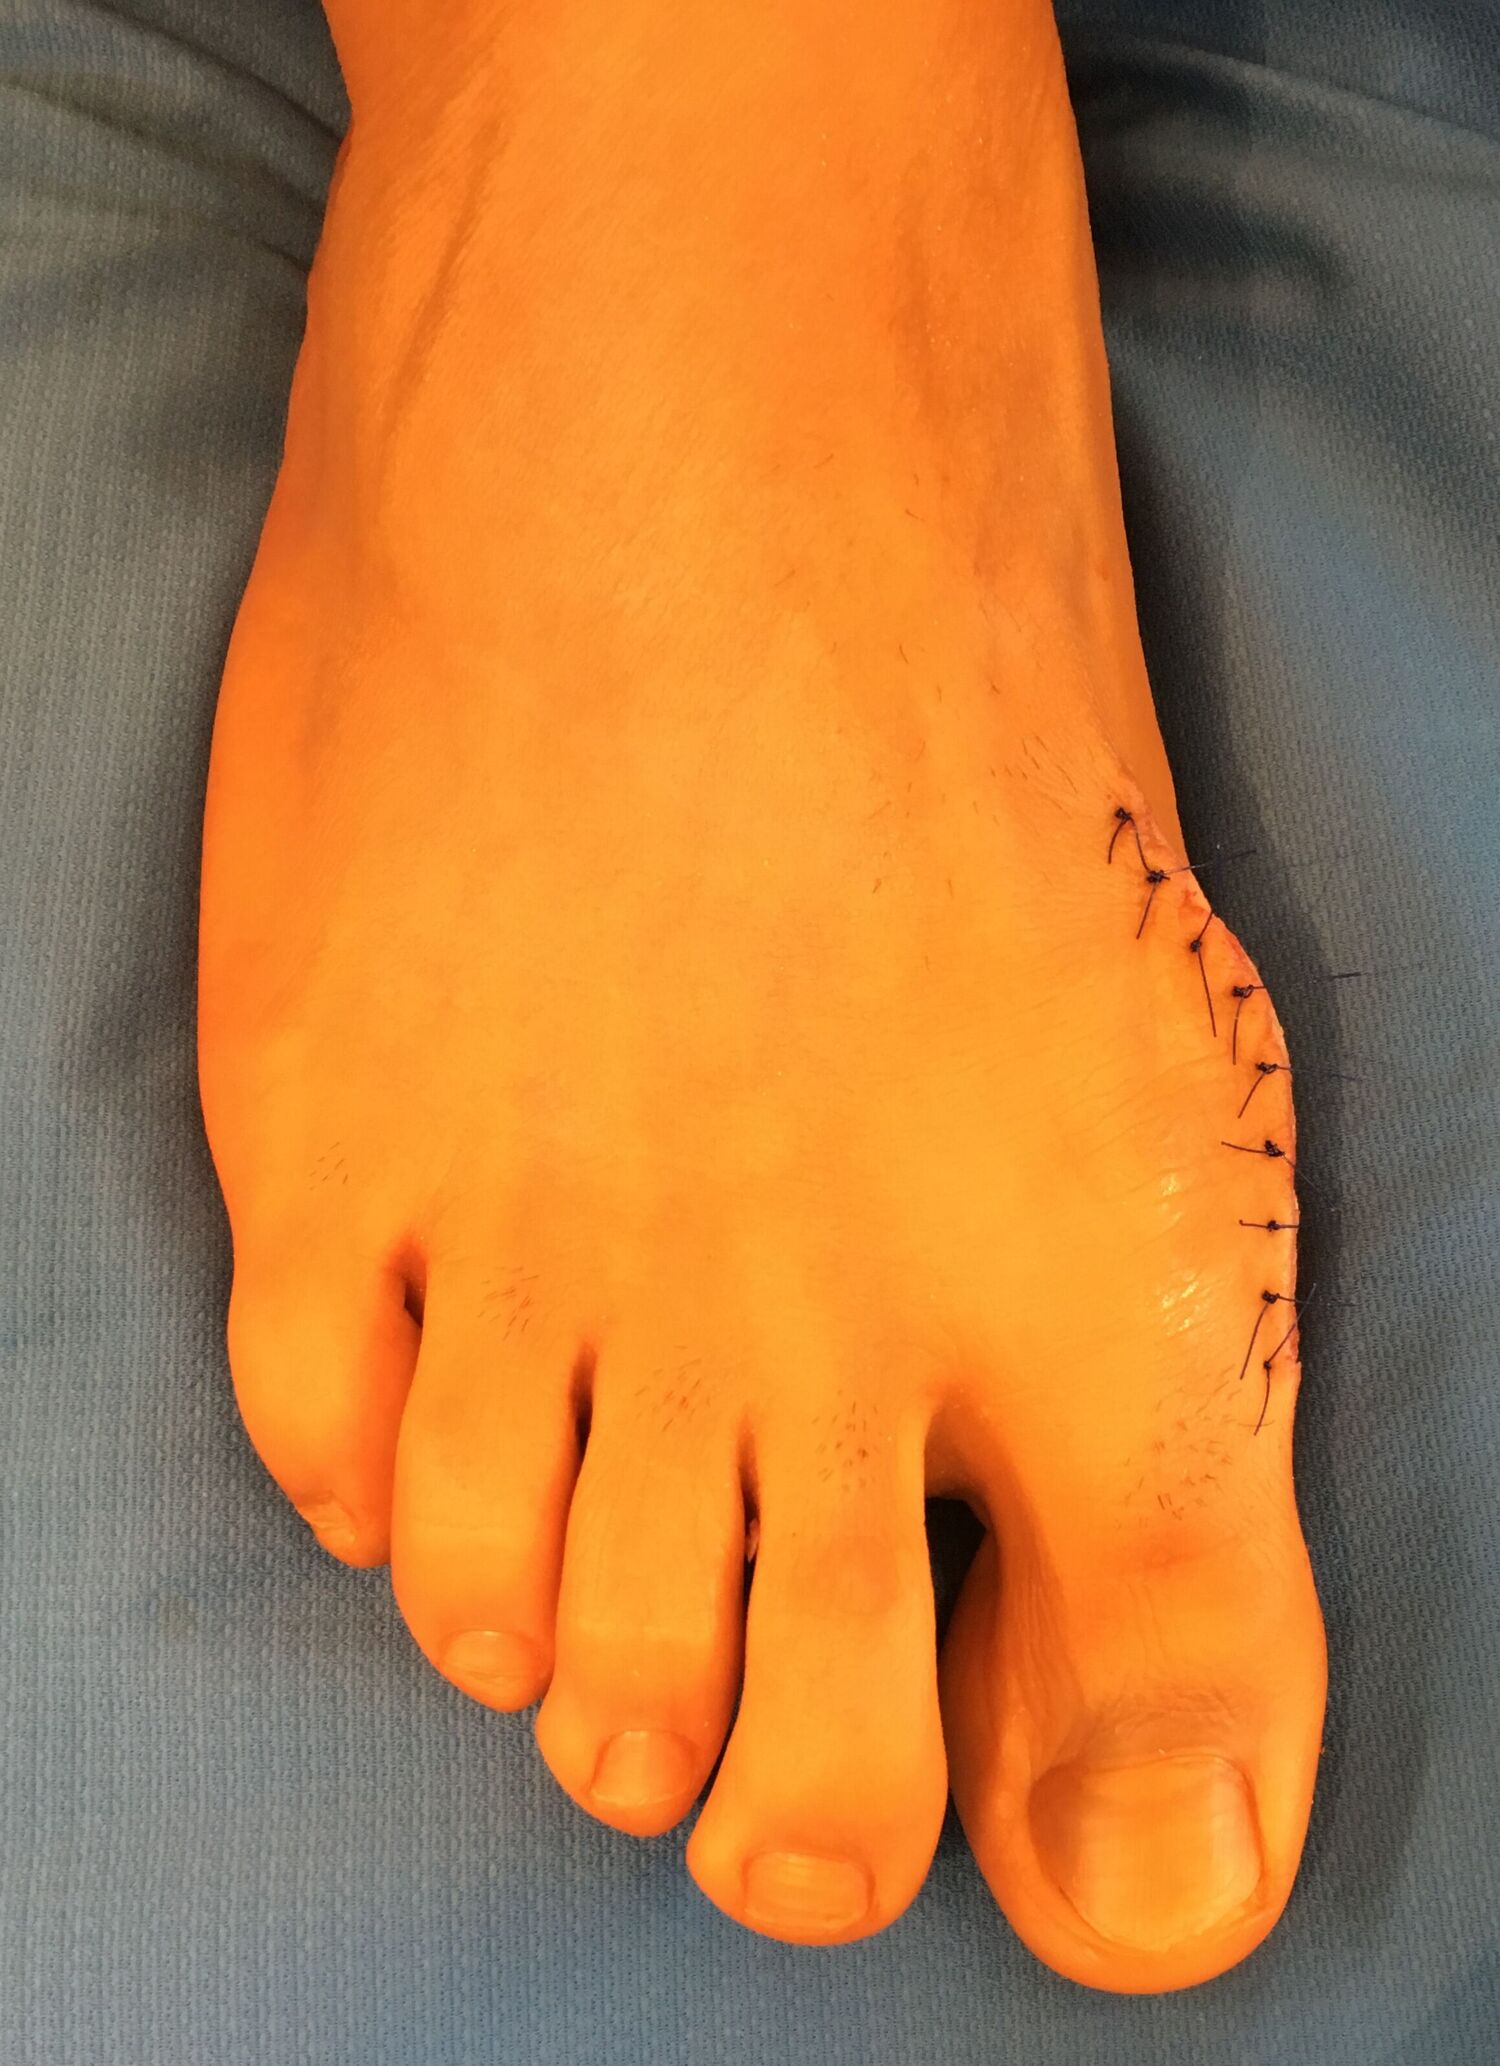

Die Lapidusarthrodese

Bei höhergradigen Fehlstellungen liegt häufig eine Instabilität des 1. Fußwurzelgelenkes vor. In diesen Fällen wird die Fehlstellung durch eine Fußwurzelversteifung korrigiert.

Zunächst werden die gelenkumgebenden Weichteile gelockert und der knöcherne Vorsprung des 1. Mittelfußknochens abgetragen. Nach Darstellung des 1. Mittelfußgelenkes wird der Gelenkknorpel entfernt und der Knochen angefrischt. In korrigierter Stellung erfolgt die Fixierung mit einer Platte und Schrauben.